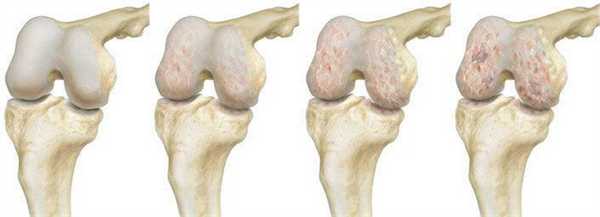

Динамика разрушения хрящевой поверхности.